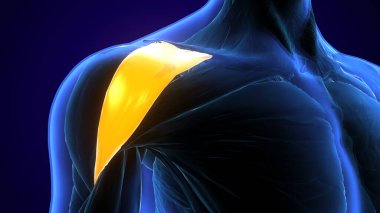

İnsan iskeleti anatomisi Scapula Kemiği Tıbbi Konsept için 3D Hazırlama

İskeletanatomiçene kemiğiyarım ayboyunlomberetmoidcapitateAltkısmınıHamate3d oluşturmaGöğüs kafesi3B illüstrasyoncarpalsağız sapımetakarplaralın kemiğiApendiküleruyluk kemiğioksipital kemikBurun kemiğikemiğigöğüs kemiğinin gövdesiayak kemikleriyarıçap kemiğiparietal kemikeksenel iskeletKalça kemiğilacrimal bonepalatine boneproximal phalangesinferior nasal conchaintermediate phalangesdistal phalangesclavicle bonekaval kemiğiBurun kıkırdağıkol kemiğikürek kemiğiBenzer İçerikler